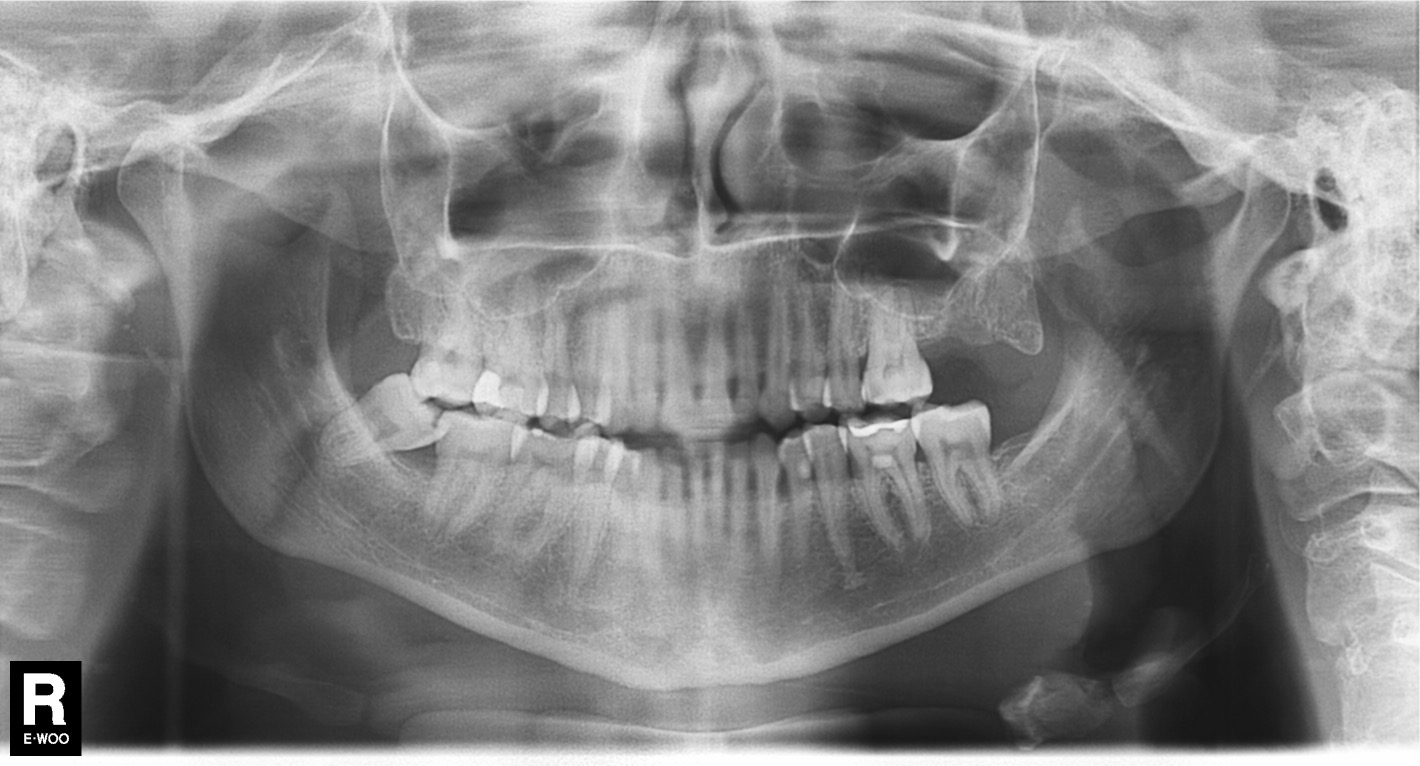

Zie foto

Deze foto is nu van nu

Zie foto’s van nu